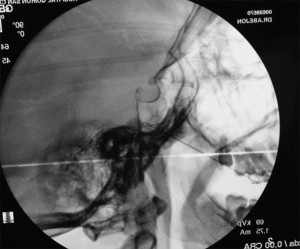

El paciente se coloca en decúbito supino, con la cabeza ligeramente en hiperextensión. Con el arco de fluoroscopia en posición anteroposterior AP se rota en dirección caudal hasta obtener una visión submentoniana, realizando entonces proyección oblicua ipsilateral (10-15º) hacia el lado a tratar hasta que se encuentre el foramen oval. Una referencia útil, si resulta complicada la visualización del mismo, es trazar una línea imaginaria que una la apófisis estiloides de la mandíbula con la última pieza dentaria del maxilar superior. Si las ramas a tratar son la segunda y la tercera dirigiremos la aguja en visión túnel hacia la parte central del foramen oral. (entrando a nivel de la piel a dos dedos de la comisura bucal) y si es la primera rama, dirigiremos la aguja en visión túnel a la parte interna de dicho foramen (a tres dedos de la comisura bucal), por la localización de las ramas como se ha descrito en anatomía. Una vez localizado el foramen oval y señalizado el punto de entrada en la piel, se fija la cabeza del paciente para evitar la movilización de la misma durante el procedimiento y se procede a realizar una sedación profunda.. Una vez introducida la aguja y antes de profundizar, es conveniente introducir un dedo en la boca del paciente para asegurarnos que no se ha perforado la mucosa oral, lo que conlleva el riesgo de contaminación y la posibilidad de producir una meningitis. La aguja se avanza hasta la entrada en el agujero oval, que se suele apreciar un aumento de la resistencia, en ese momento se realiza una proyección lateral para comprobar la profundidad y la correcta colocación en la cavidad de Meckel, no debiendo superar la punta el plano del clivus. Una vez comprobada la adecuada situación se procede a la estimulación, primero se realiza una estimulación motora a 0.6v comprobando que no existe contracción del masetero si se obtiene estímulo motor, la aguja se avanza cuidadosamente 1 ó 2mm. Se procede a despertar al paciente y con un estímulo sensitivo se comprueba la parestesia en la rama adecuada. Nuevamente se profundiza la sedación y se realiza la lesión. Estimulación sensitiva: (50Hz) desde notar parestesias entre 0.1- 0.5v. Estimulación motora: (2Hz) no debe haber contracción del musculo masetero con 0.7-1v (excepto si se está estimulando la tercera rama). Se realiza varias lesiones con radiofrecuencia convencional (1ª lesión 60s a 60º, 2ª lesión 60s a 65º y 3ª lesión 60s a 70º).